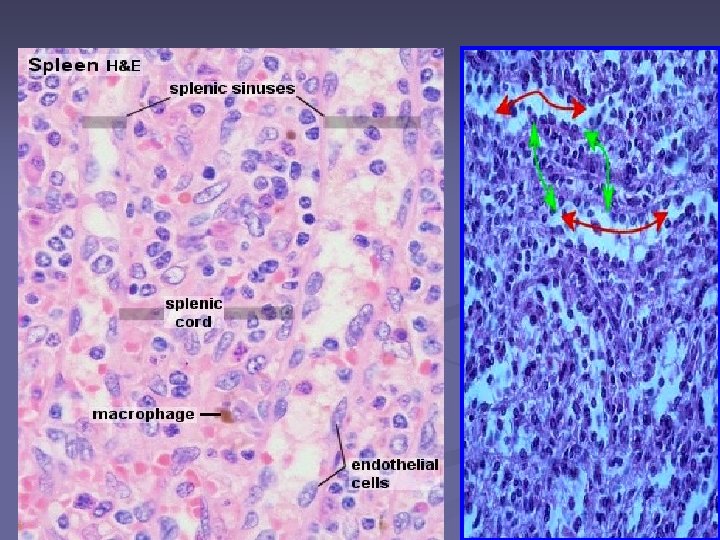

Pulpa roşie -75% (~ burete, spongiu) sinusuri venoase - cordoanele celulare Billroth Rol: filtrează singele

n Sinusuri venoase splenice n Primesc sangele din arterele penicilate/ capilarele postarteriale lumen larg, neregulat, anastomozate -un perete discontinuu - m. bazala discontinuă –endoteliu discontinuu - spatii care faciliteaza schimbul dintre sinusoide si tesutul din jur; n n • cel endoteliale - alungite (în axul lung al vasului) - sunt învelite de fibre de reticulină dispuse concentric, care se continuă cu fibrele de reticulină din stromă n Sinusurile venoase splenice - Venule → Venele pulpei → Vene trabeculare → Vena splenică

n. Cordoanele celulare splenice Billroth (interstiţiu) - reţea de fibre de reticulină şi cel reticulare în ochiurile reţelei : hematii, leucocite, limfocite, monocite, plasmocite, macrofage - fagociteaza resturile - eritrocitelor imbatranite - fagociteaza antigenii circulanti In conditii patologice (leucemii), pot apare megakariocite, eritroblaste -

Pulpa roşie n Circulaţia deschisă favorizează funcţia de filtrare a sangelui